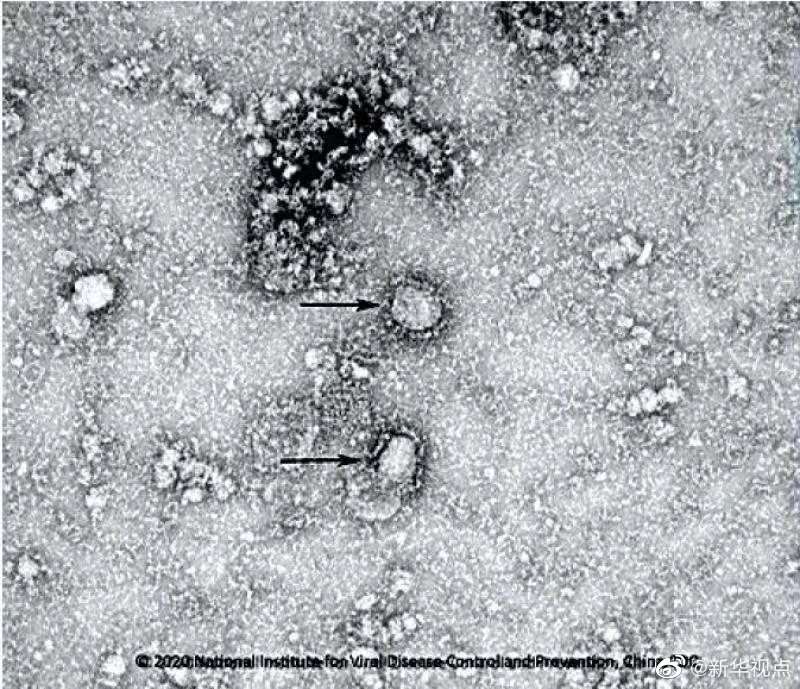

國(guó)家病原微生物資源庫(kù)于2020年1月24日發(fā)布了由中國(guó)疾病預(yù)防控制中心病毒病預(yù)防控制所成功分離的我國(guó)第一株病毒毒種信息及其電鏡照片、新型冠狀病毒核酸檢測(cè)引物和探針序列等國(guó)內(nèi)首次發(fā)布的重要權(quán)威信息,并提供共享服務(wù)??床《尽罢嫒荨薄ㄓ浾咛飼院?、王秉陽)

好消息!中國(guó)疾控中心成功分離我國(guó)首株新型冠狀病毒毒種,它長(zhǎng)這樣!-新華網(wǎng)